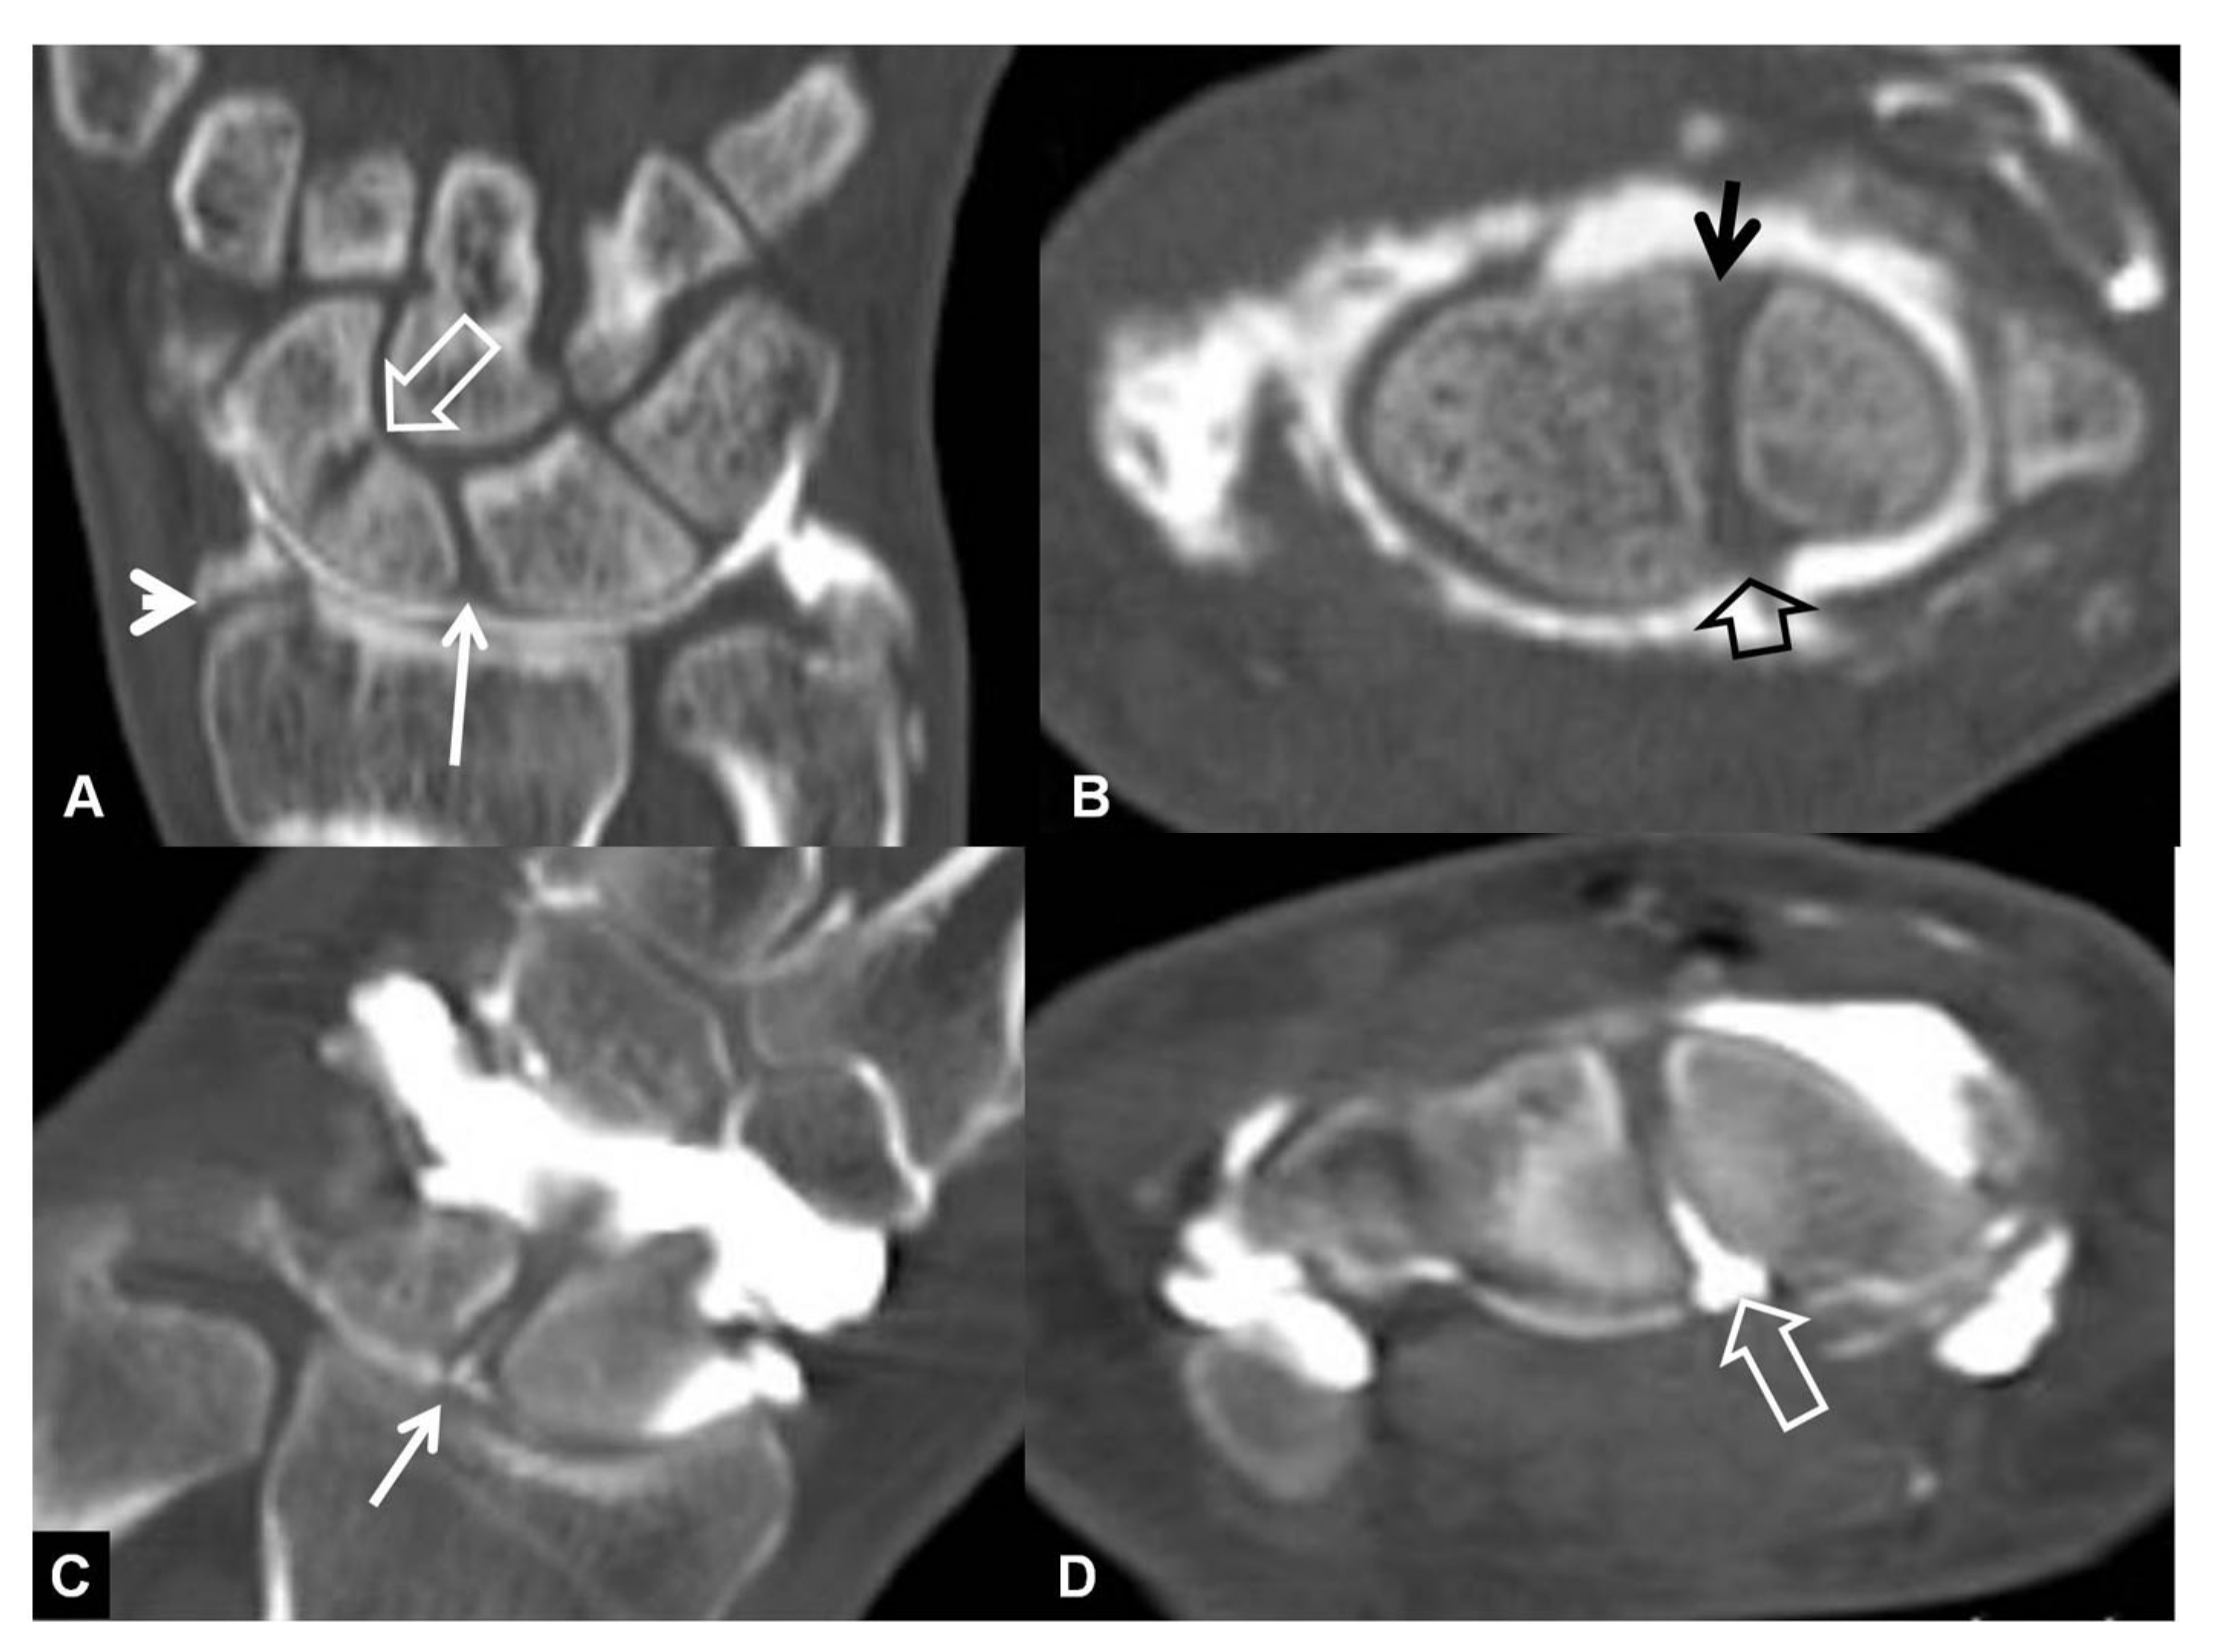

Figure 8.

A 33-year-old with a history of scaphoid fracture. (A) Coronal CT-arthrographic image showing the scaphoid pseudarthrosis (open arrow), a radial styloid process fracture (arrowhead) and an intact scapholunate ligament (arrow). (B) Axial CT-arthrographic image showing the intact dorsal (arrow) and palmar (open arrow) parts of the scapholunate ligament. A 56-year-old male patient who was involved in a motor vehicle accident 1 year prior to current imaging. Coronal (C) and axial (D) CT-arthrographic images showing a tear at the membranous (arrow) and palmar (open arrow) parts of the scapholunate ligament.